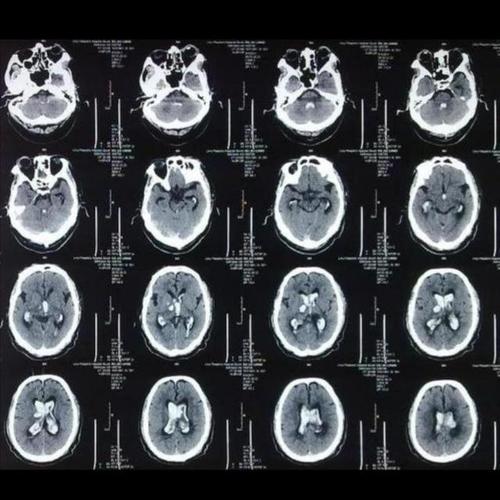

脑出血片子图片解析

脑出血片子图片解析,脑出血检查报告单图片

脑部ct怎么看图解

脑出血ct影像表现图片

脑出血ct图片解说图

脑出血图片ct

脑出血ct